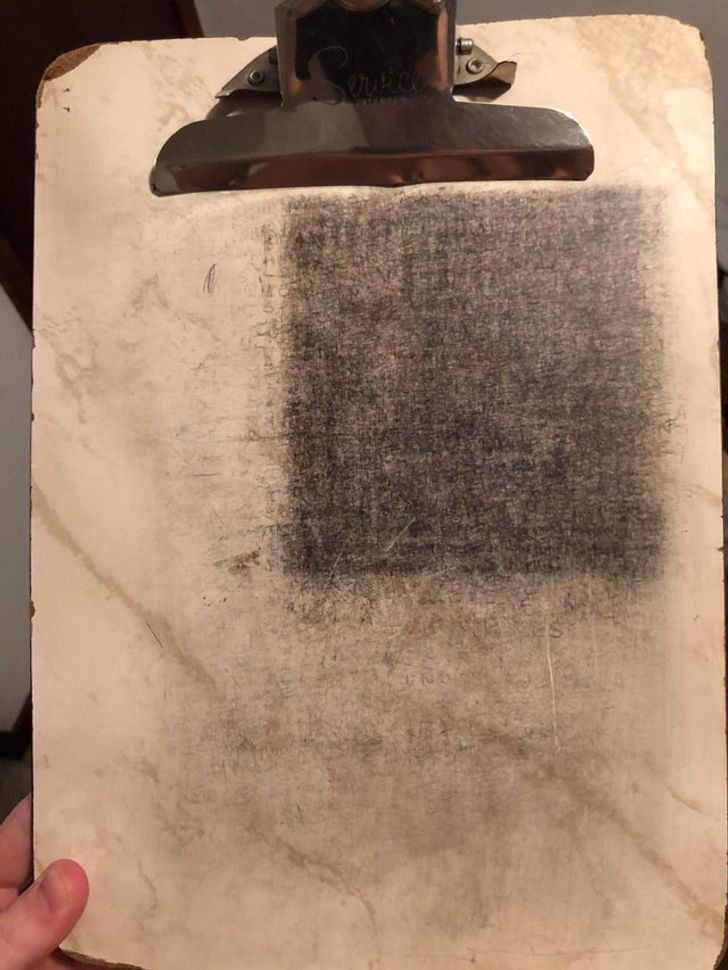

Як виглядатиме голова, якщо в неї вживити пристрій, який допомагає контролювати епілептичні напади

«Моя голова після останньої операції. Мені вживили пристрій контролю над епілепсією».